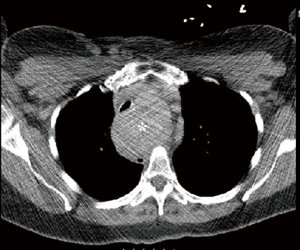

Institutional review board exemption was obtained prior to commencing this study (IRB 2014-12-15). Consent from the patient was not required because the information is recorded by the investigator in such a manner that research participants cannot be identified, directly or through identifiers linked to the research participant. Between 2012 and 2015, 280 thyroidectomies were performed of which 45 (16%) had a retrosternal component. Thirty-nine out of 45 (86%) retrosternal goiters were anterior mediastinal, only one of which required thoracoscopy. Six of 45 (13%) were middle/posterior mediastinal. Out of 7 retrosternal goiter that required thoracoscopic approach, 1 was anterior mediastinal and 6 were middle/posterior mediastinal. Seven patients with large mediastinal goiters, particularly those with atypical mediastinal extension (paratracheal, retroesophageal, etc.) were evaluated by a thoracic surgeon preoperatively and selected for simultaneous unilateral thoracoscopy and cervical thyroidectomy (Table 1, Figures 1,2) . Patient age range was 57 to 91. Six of the patients were female. Only one of the patients had clinical hyperthyroidism while the remainder of patients was euthyroid. Two patients had goiters that extended into the right paratracheal region, two patients had goiter extension to the left paratracheal/subaortic region, one patient had goiter extension to the retrotracheal region and one patient had extension of the left thyroid lobe to the right hemithorax via the retroesophageal plane. The last patient had a large substernal calcified thyroid goiter extending from the left lobe. Seven patients had respiratory symptoms with stridor and tracheomalacia. Two patients required perioperative mechanical ventilation and one required an emergency tracheostomy on presentation. The patient with a retroesophageal goiter also had symptoms of dysphagia. The patient with clinical hyperthyroidism presented with new onset atrial fibrillation. None of the patients had malignancy. All patients underwent preoperative stabilization prior to elective resection.